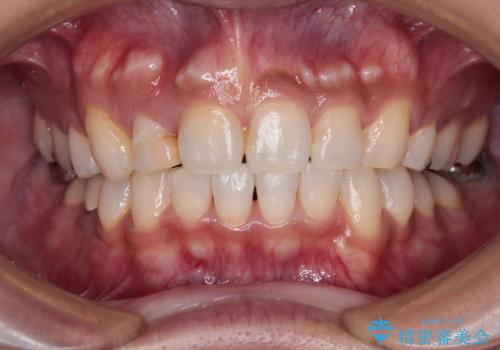

【モニター】八重歯と正中のずれた歯列 片顎抜歯のワイヤー矯正